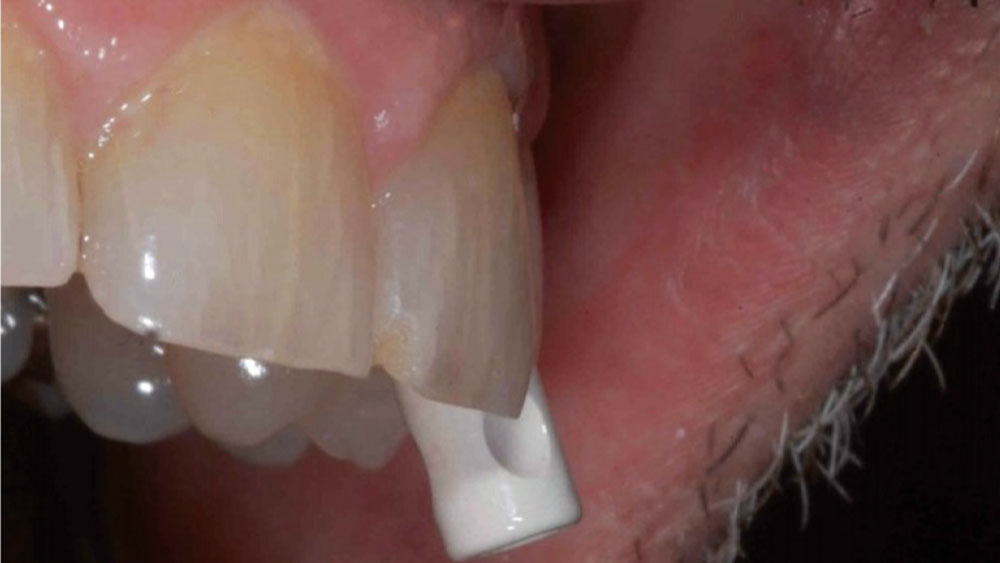

This case is an example of an ideal clinical situation for dentists who are new to placing implants in the esthetic zone. The patient requested treatment for a fractured upper lateral incisor. After extraction, grafting and healing, ample bone and soft tissue were present, and an implant was placed in optimal position for an esthetic result. The screw-retained restoration predictably restored form and function, illustrating the beautiful results that can be achieved by observing simple surgical and prosthetic guidelines.